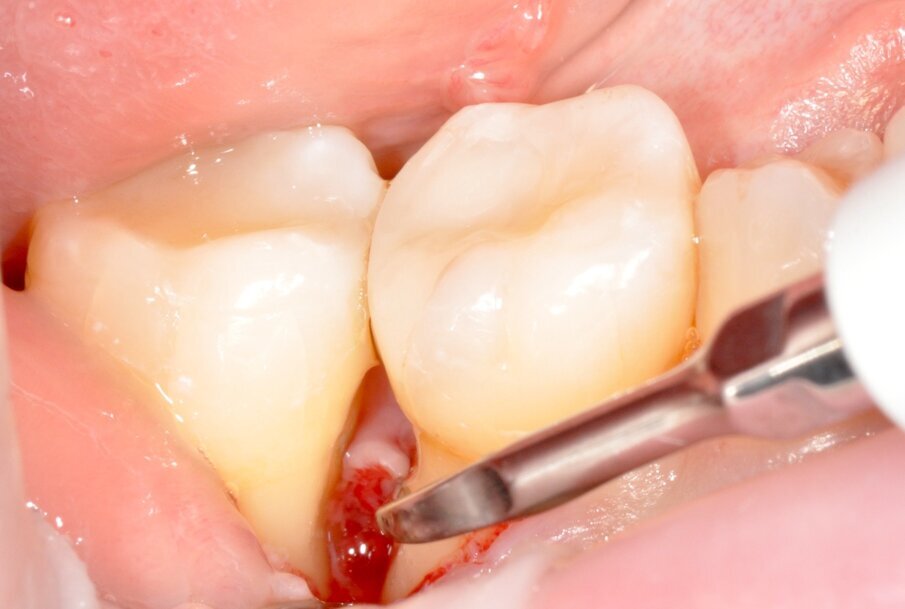

Tuttavia, nei siti DV e MV degli elementi 4.6. e 4.7 si riscontra nuovamente BOP e SOP positivo. Si decide dunque di effettuare un intervento di chirurgia ricostruttiva, finalizzato alla chiusura del difetto intra-osseo e programmato ad una settimana dalla seduta di richiamo di igiene orale professionale (GBT®). Dopo uno sciacquo per 60 secondi con collutorio a base di Clorexidina 0.12% e Cloruro di Cetilpiridinio (Paroex® GUM®), si esegue anestesia locale plessica con Articaina 4% con adrenalina 1:100.000 e disegno di un lembo M-MIST (Modified-Micro Invasive Surgical Technique)5. La scelta di questo tipo di lembo è volta alla massima preservazione della vascolarizzazione del sito chirurgico e al mantenimento della papilla interdentale.

Fig. 4 - Sondaggio DV dell’elemento 4.6 di 9 mm.